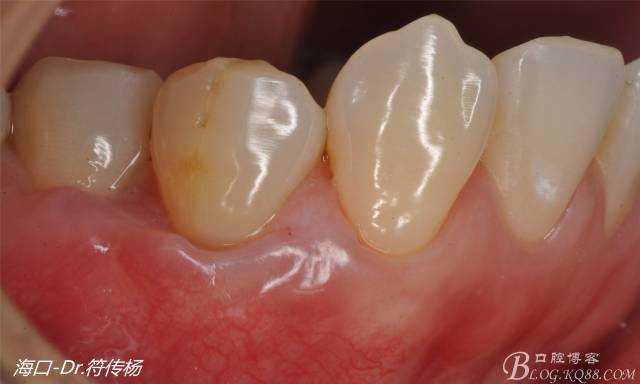

術(shù)后十天牙齦一期愈合